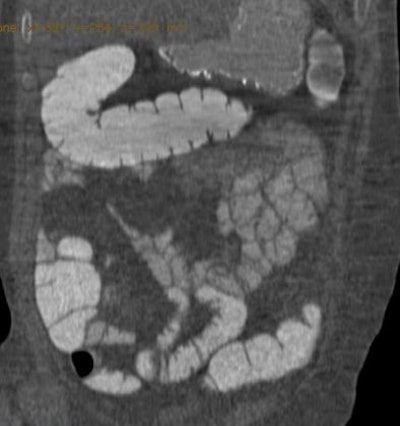

| CT colonography from group A (same-day preparation). The coronal image shows good and homogeneous fecal tagging from the proximal to the distal colon. Image courtesy of Dr. Delia Campanella. |